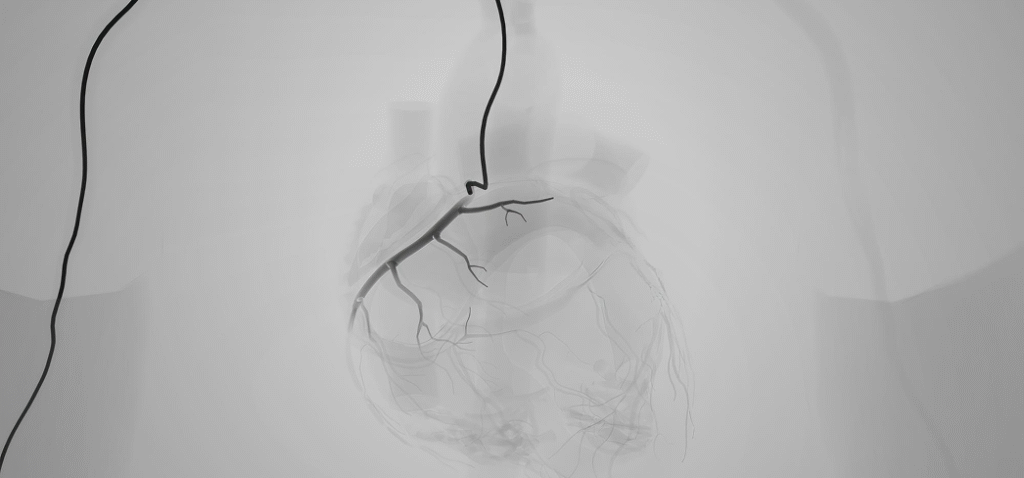

Angiography is a specific imaging method designed for diagnostic purposes. It allows doctors to visualize the inside of blood vessels and internal organs clearly.

It involves injecting a contrast dye (iodine-based) into the bloodstream and then taking X-ray images, or angiograms, to trace the blood flow.

When the procedure explicitly focuses on the blood vessels supplying the heart muscle, it is called coronary angiography in Dubai (or simply heart angiography in Dubai). This diagnostic tool is the gold standard for checking the heart arteries for blockages, narrowings, or other structural issues.

The resulting images reveal:

- The precise location and severity of any blockages or narrowings in the coronary arteries.

- The presence of aneurysms (bulging of the vessel wall) or blood vessel malformations.

- The functionality of heart chambers and valves (often done simultaneously with ventriculography).

Imaging: X-rays are taken as the dye flows through the vessels. This creates the angiogram images, clearly highlighting any areas of narrowing.